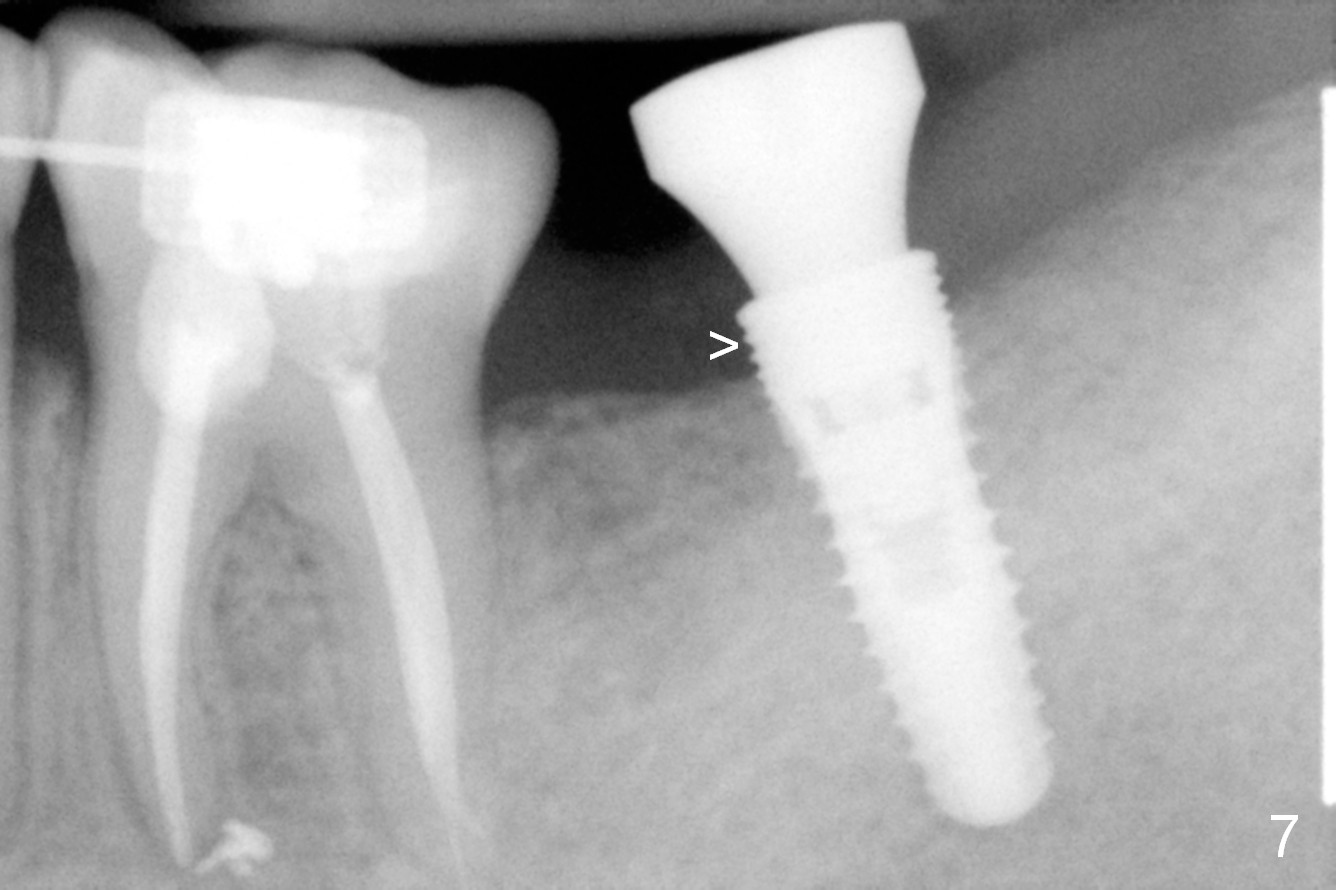

Planning gives the surgery and assistants confidence. Implant placement seems to be more smoothly. A preop PA (Fig.1) shows that the periapical radiolucency of the neighboring tooth #19 disappears. Removal of the residual roots of the teeth #17 and 18 (Fig.1 *) gives rise to a nice surgical field (Fig.2, the sockets packed with Clindamycin soaked gauze). Immediate implant osteotomy is formed as mesial as possible of the wound. Attention is being paid to buccolingual trajectory when the first pilot drill is used (not shown). An intraop PA is taken with a 3.8 mm tap in place to confirm the depth of the osteotomy relative to the inferior alveolar canal (Fig.3). A 4.5x12 mm implant is placed as planned (Fig.4). The elongated wound (mesiodistally) allows the wound to approximate around the implant/healing abutment with sutures (Fig.5). The gingiva heals 8 days postop (Fig.6). The 1st 4 coronal threads remains outside the bone 3.5 months postop (Fig.7 >). It appears that less thread exposure 1 year 7 months postop (Fig.8), suggesting bone growth. To prevent periimplantitis and facilitate restoration, place 2nd molar implant as deep as possible with slightly shorter implant.